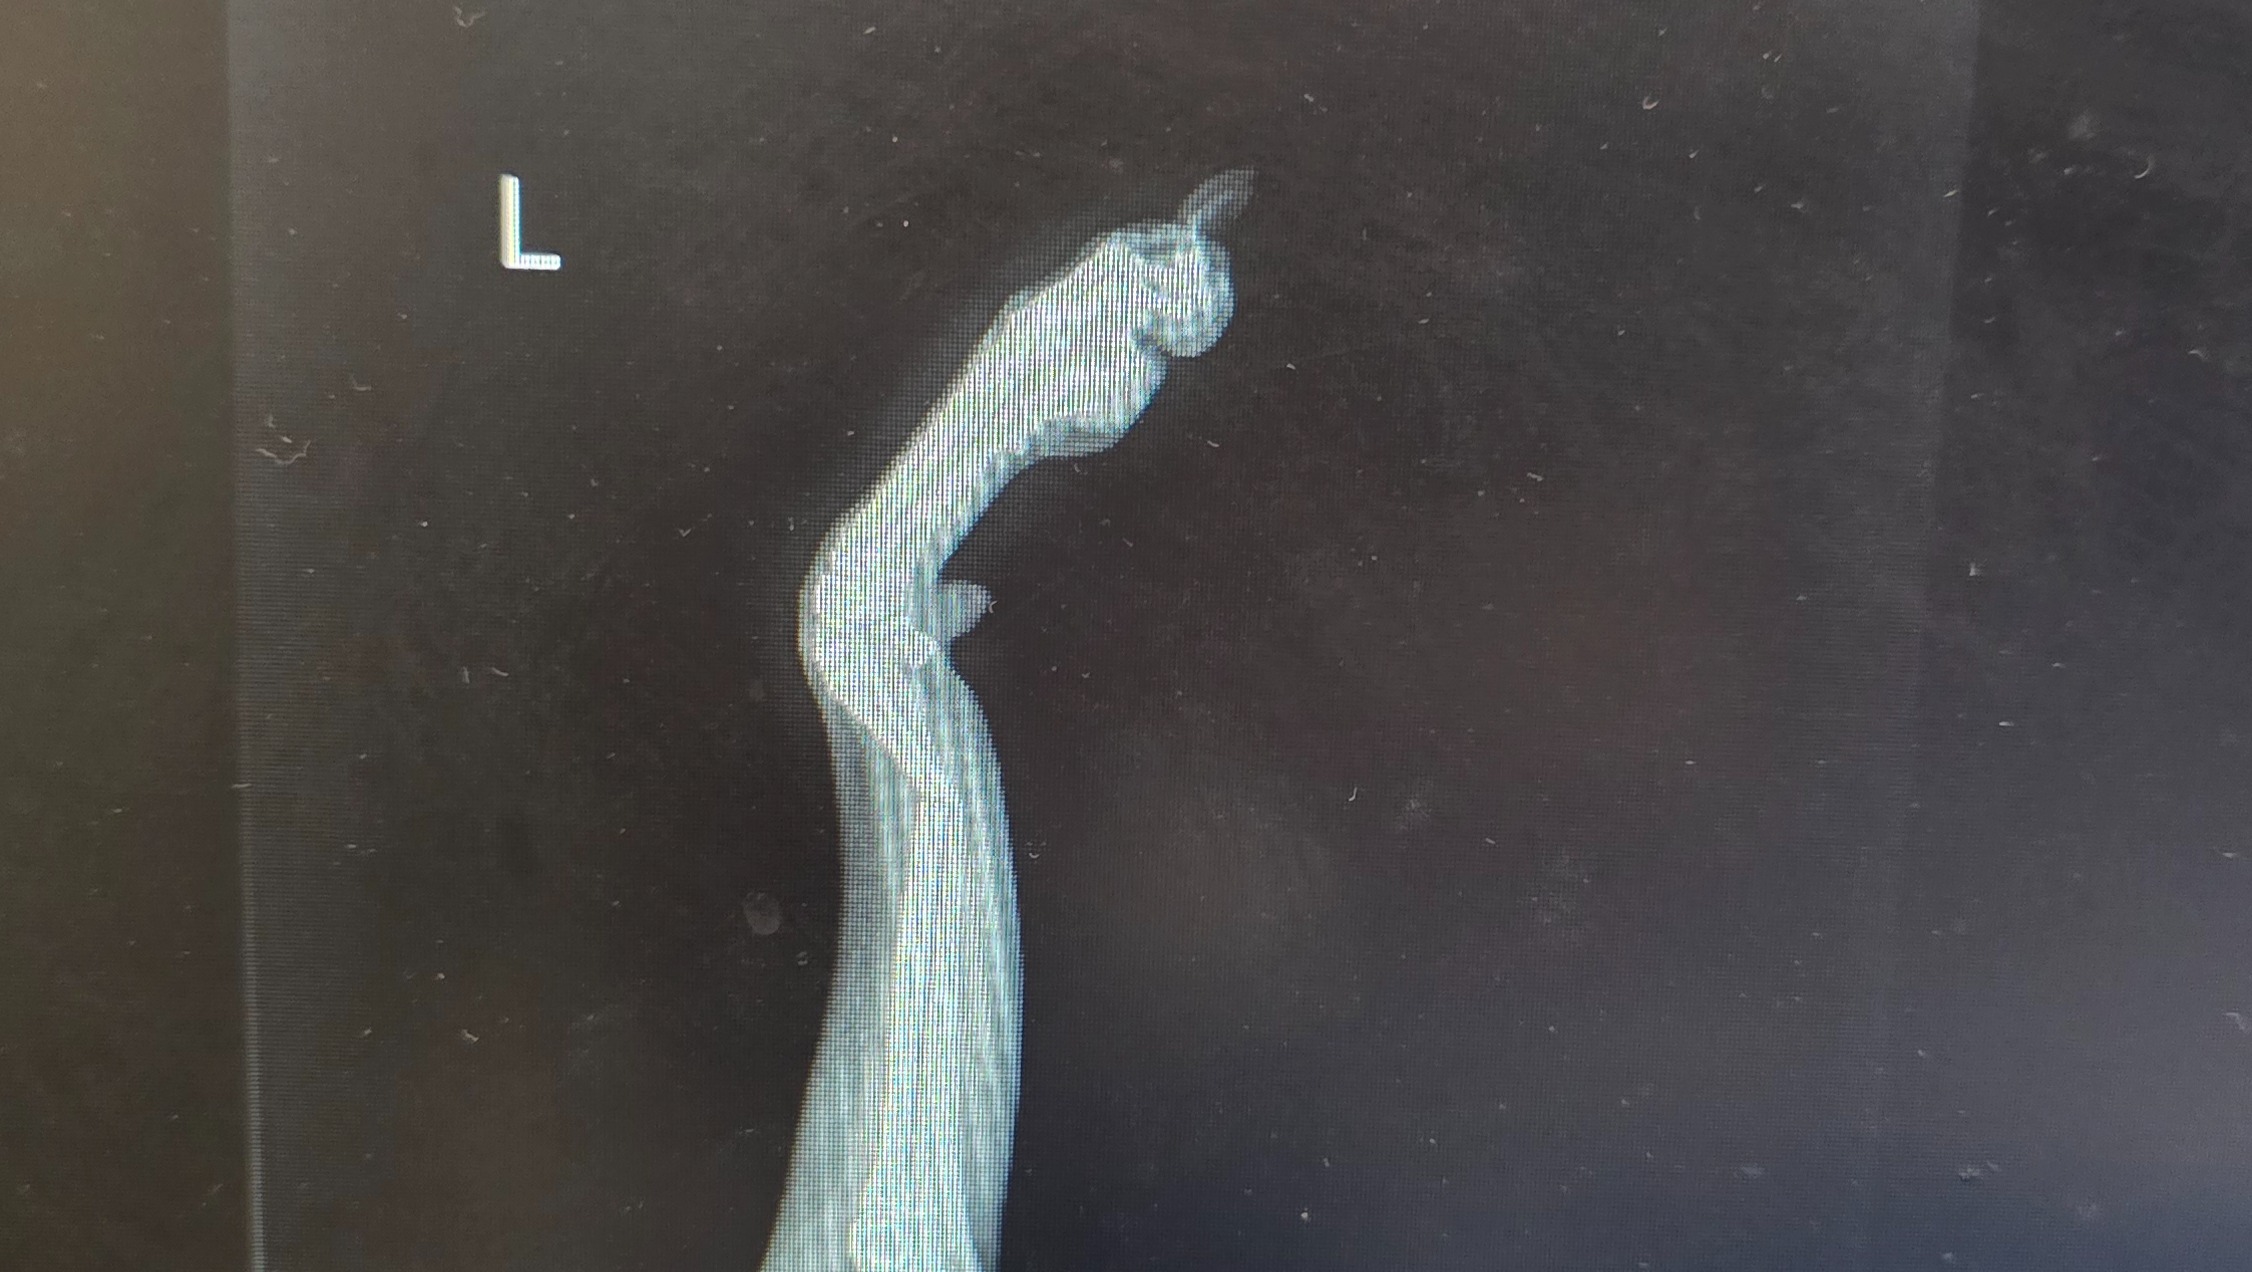

And of course, he is a dog. And puppies are wild. I wasn't there to witness but he apparently jumped from the top of my Oma's bed to the floor and potentially slipped and landed wrong. There were so many clothes on the floor, so he may have just landed wrong. I rushed him to the ER and as a result, he managed to fracture both of his front legs (radial and ulna bones).

They had to sedated him for the xrays because he wouldn't stop screaming in pain

He ended up with a splint and an Ortho consult for Wednesday.